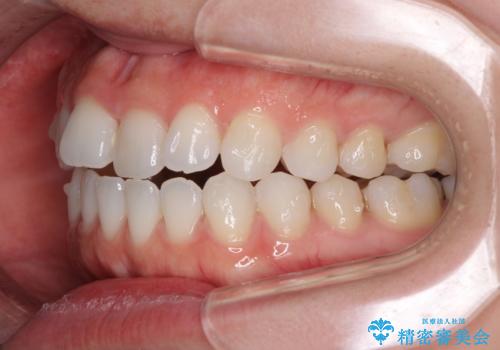

- 上下の前歯の反対咬合を気にして来院された患者様です。

インビザラインを用い、下顎はIPR(歯と歯の間を削る)と歯列全体を後方に移動させ、上顎は前歯を持ち上げることで、反対咬合を改善していくこととしました。

インビザラインによる反対咬合の改善は、上の歯が下の歯を乗り越えていく期間に咬み合わせが非常に不安定となり、治療が長期化することがあります。

こちらの患者様も、一時的に前歯でしか咬めない時期がありましたが、比較的早く咬み合わせが安定し、1年ほどで治療を終えることができました。